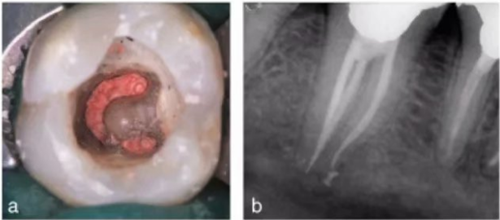

使用牙周探針對(duì)牙冠或牙頸部形態(tài)進(jìn)行臨床檢查有助于發(fā)現(xiàn)額外的牙根。一個(gè)額外的牙尖(副磨牙結(jié)節(jié),tuberculum paramolare)或明顯突出的遠(yuǎn)頰或遠(yuǎn)舌小葉,伴有頸部的突出,可能表明存在額外的牙根。遠(yuǎn)舌根的根管口位于主要的遠(yuǎn)中根管的近舌側(cè),因此開髓洞型需要預(yù)備成矩形或梯形。使用牙髓探針仔細(xì)檢查髓室底的暗色的發(fā)育溝,可以精確的定位遠(yuǎn)舌根根管口。

使用手術(shù)顯微鏡是非常有幫助的,特別是在那些根管口被鈣化物覆蓋的病例中,這些鈣化物可以使用超聲尖或長(zhǎng)柄小球鉆輕松去除(圖 14a-d)。